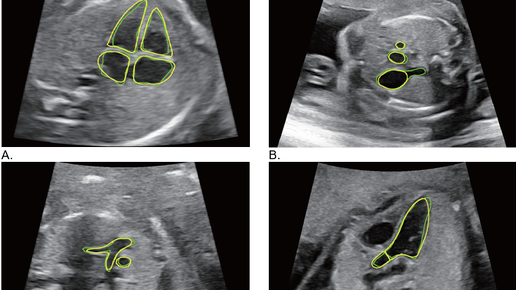

HeartAssistTM: Инструмент для автоматической классификации и измерения параметров, используемый для оценки сердечной деятельност

Аннотация Цель: Оценить применимость и надежность инструмента HeartAssistTM, который автоматически выполняет сложную классификацию срезов сердца плода и измеряет структуры сердца плода. Методы: Эксперты-исследователи получили 10 изображений сердца плода и измерили каждый параметр вручную и с помощью HeartAssistTM. Программа HeartAssistTM автоматически классифицировала полученные срезы сердца плода и измерила параметры. Была проведена оценка допустимой частоты классификации и точности аннотирования...